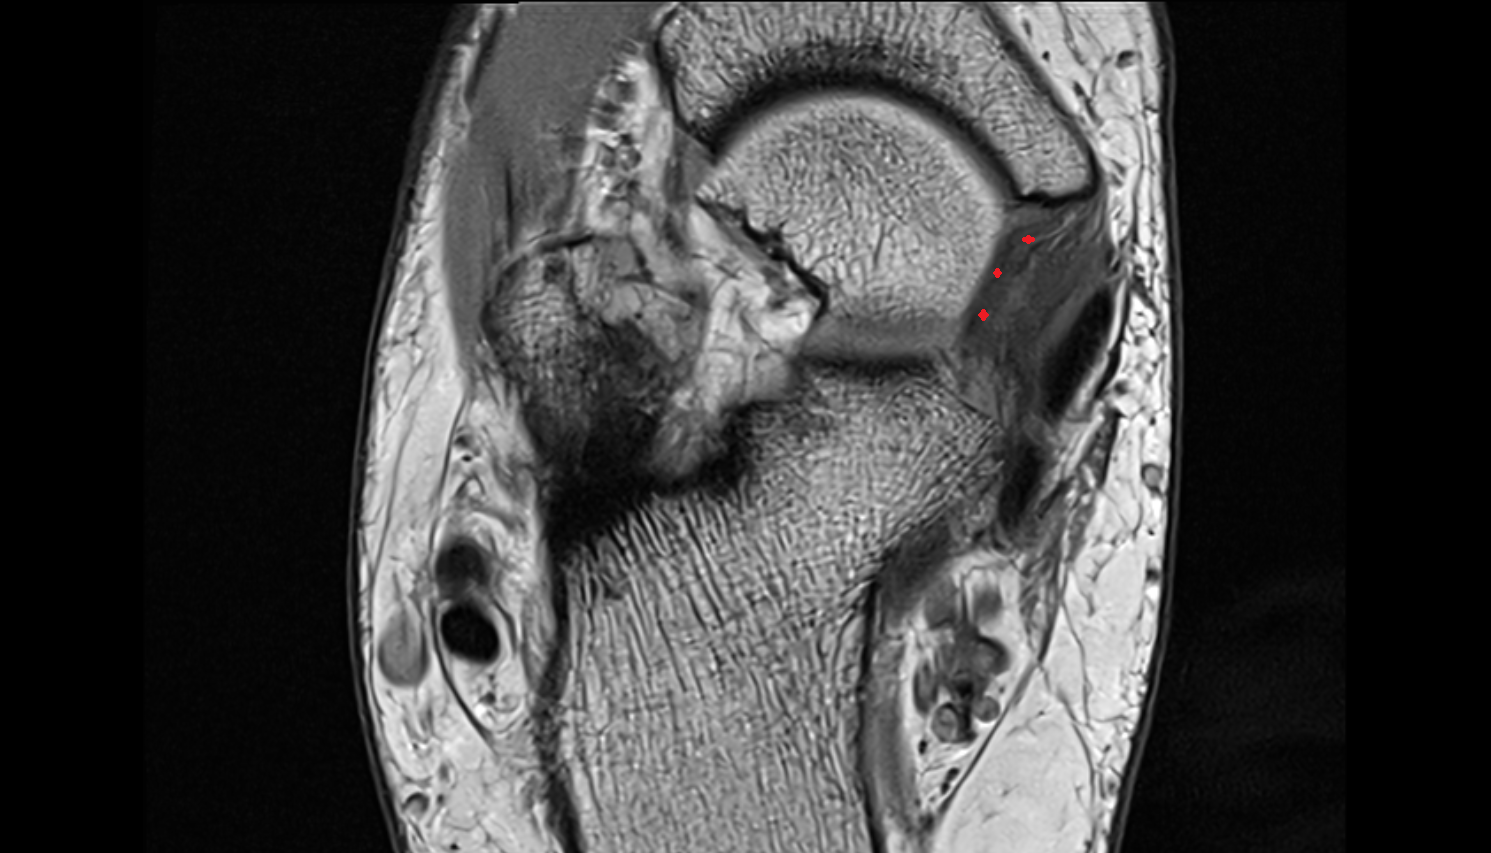

- Temporomandibular joint

- Articular disc of temporomandibular joint

- Mandibular condyle

- Superior head of lateral pterygoid muscle

- Inferior head of lateral pterygoid muscle

- Lateral pterygoid muscle